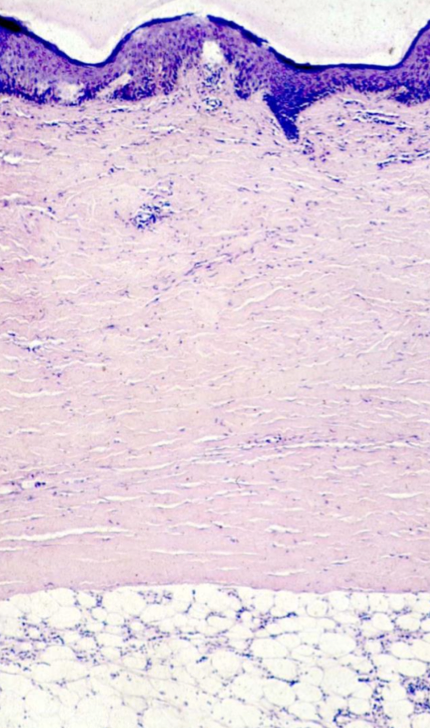

Chronologie histologie sclérodermie

Au début :

Plus tard :